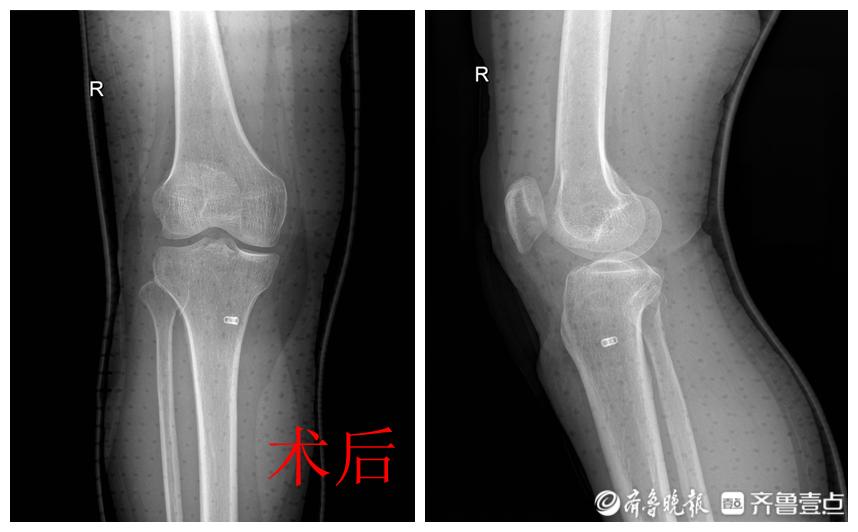

近日,胜利油田中心医院关节外科、运动医学科成功开展一例膝关节镜下髁间嵴撕脱骨折三骨道缝线内固定手术。

患者郗女士,52岁,因摔伤右膝关节疼痛伴活动受限2天,由外院转入胜利油田中心医院关节外科、运动医学科。入院后行CT检查显示胫骨髁间嵴撕脱骨折(粉碎性)。关节外科、运动医学科医护团队经过全面评估、详细论证和严格评估手术指征后,在关节外科、运动医学科主任张冠宏指导下,由主治医师张金龙、梁相辰主刀,顺利为患者实施了膝关节镜下髁间嵴撕脱骨折三骨道缝线内固定手术,术后效果满意,患者目前正在康复中。